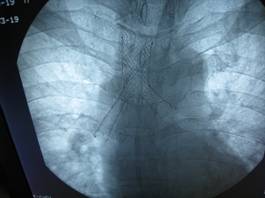

患者施某,男,49岁,1月前不明原因出现咳嗽、咯血,3月初入住我科,经支气管镜检查发现:气管近隆突处新生物,导致左右主支气管狭窄,尤其右侧明显,气管镜不能伸入。病理诊断:透明细胞肌上皮瘤。属罕见气管肿瘤,呈低度恶性。患者资料由家属送至上级医院会诊及我院全院讨论,无手术指征,因患者气道狭窄严重,随时可能因肿瘤增大出现呼吸困难及窒息,放化疗治疗因风险大暂不宜进行。我科于3月19日下午在DSA室行Y形气管支架植入术。术中,俞万钧主任负责介入操作,麻醉科严国章主任负责全麻、喉罩辅助通气及监护、DSA马霁波主任配合定位及支架释放,支架放置顺利完成,患者清醒后安返病房。

术中照片